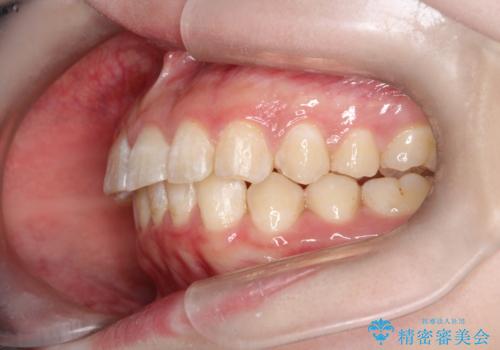

インビザラインで前歯のガタガタをきれいな歯並びへ

- 前歯のガタガタが気になるとのことで来院されました。

上顎の前歯の叢生があったのと、下あごの前歯が通常より1本欠損(先天欠損)していました。

上顎の歯と歯の間をわずかに削りスペースをつくり、並べる計画としました。インビザライン治療を選択されました。

しっかりとインビザラインを使用していただけたので、スムーズに治療を終了させることができました。